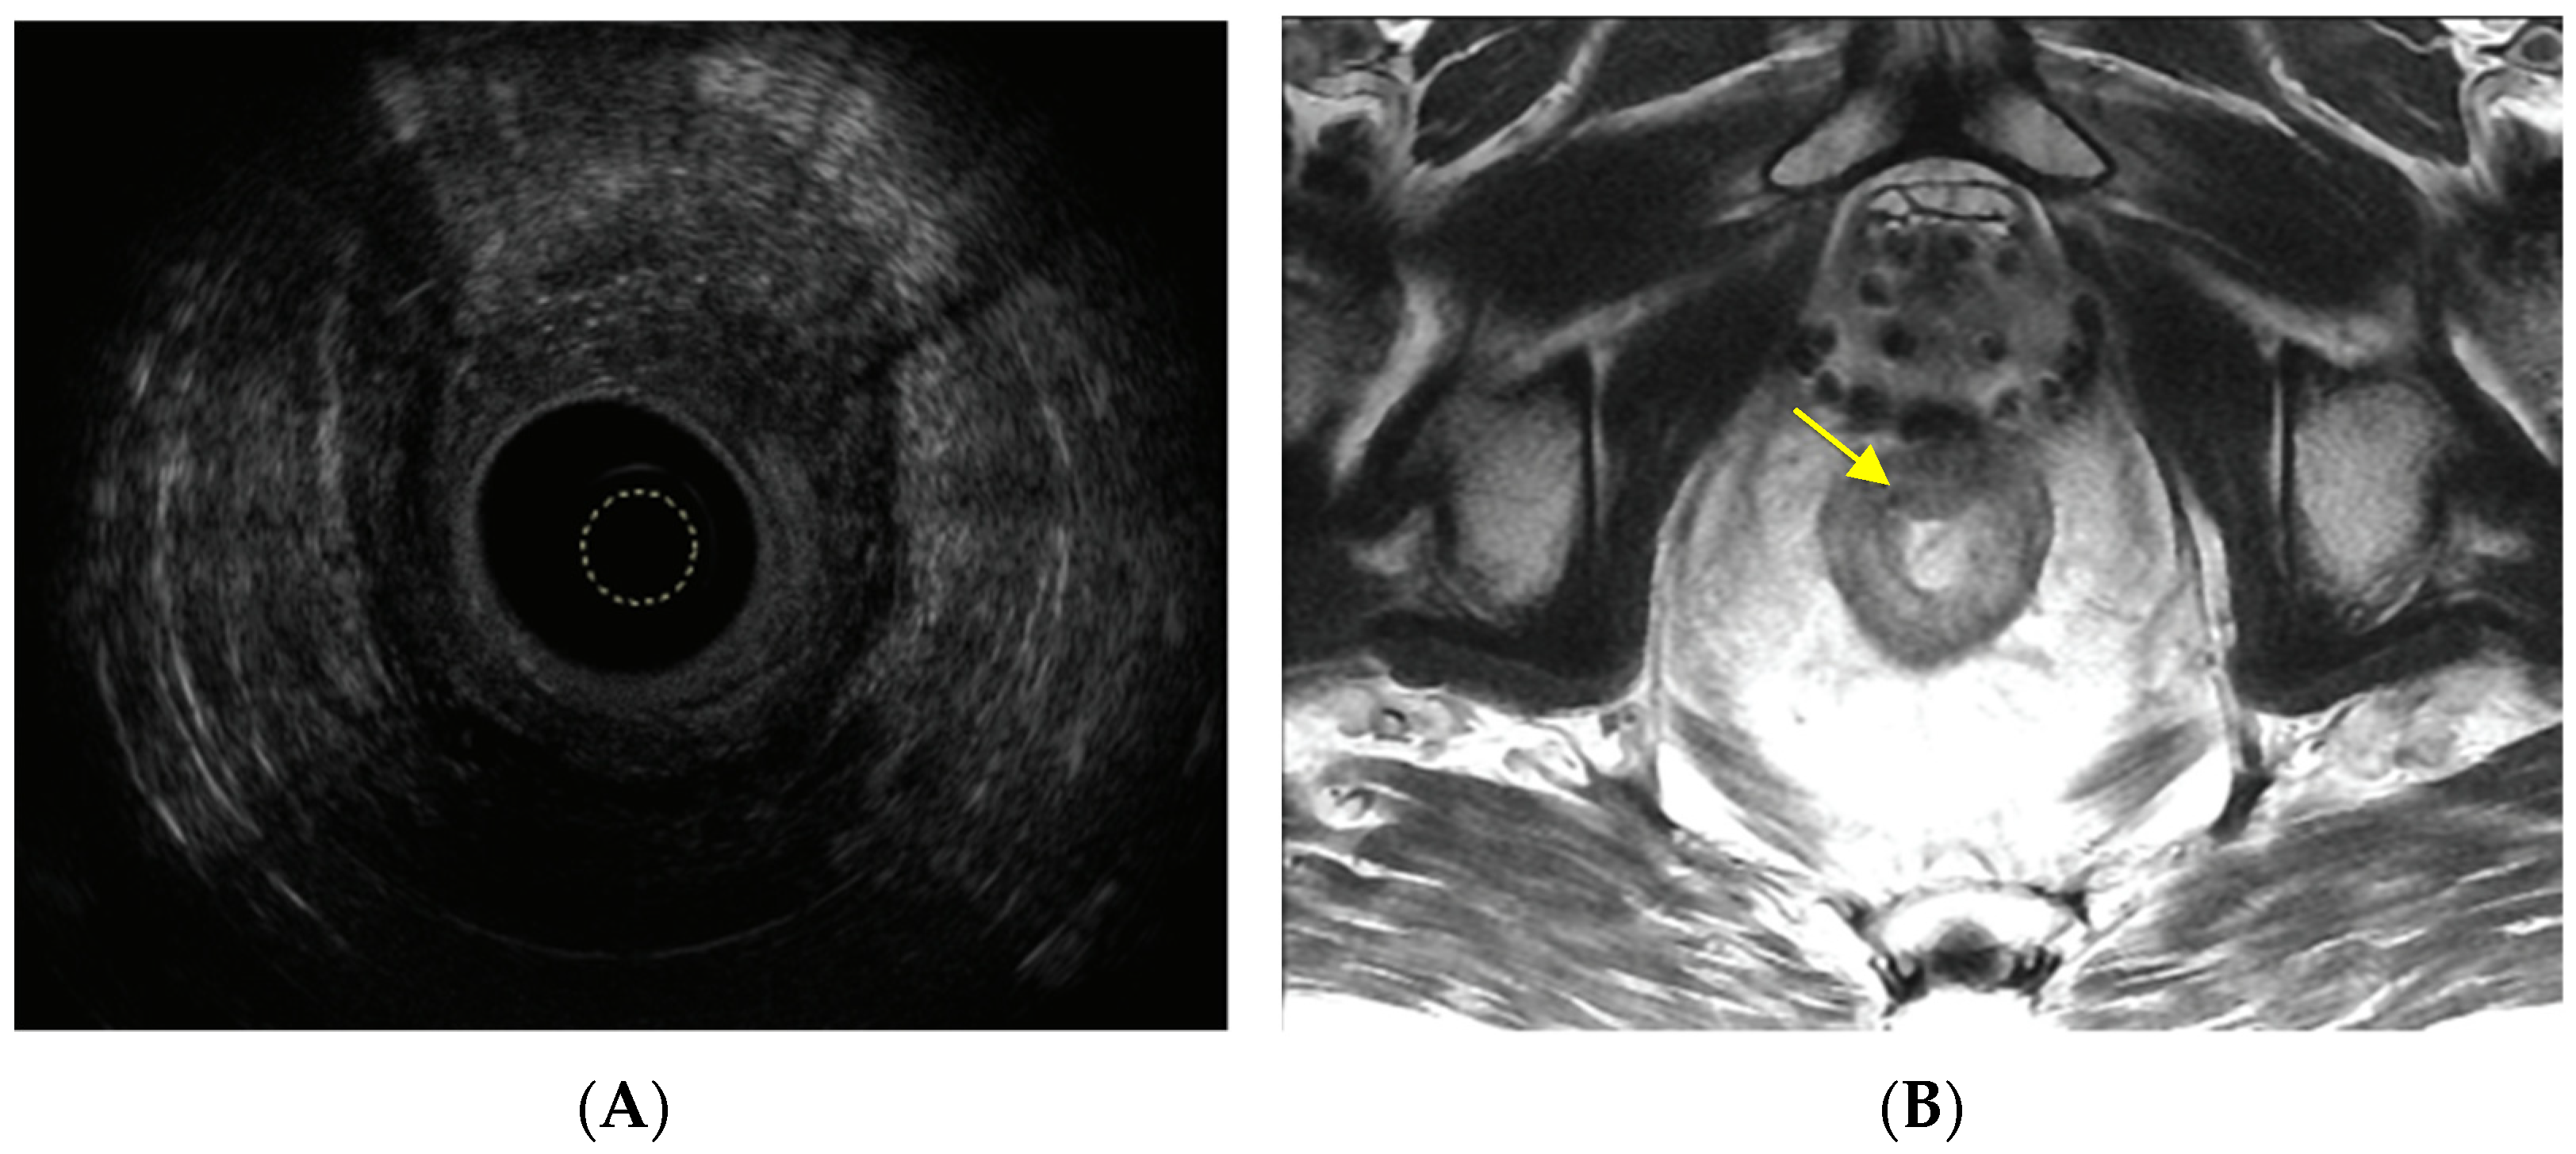

- Moreno, C.C.; Sullivan, P.S.; Mittal, P.K. MRI evaluation of rectal cancer: Staging and restaging. Curr. Probl. Diagn. Radiol. 2017, 46, 234–241. [Google Scholar] [CrossRef]